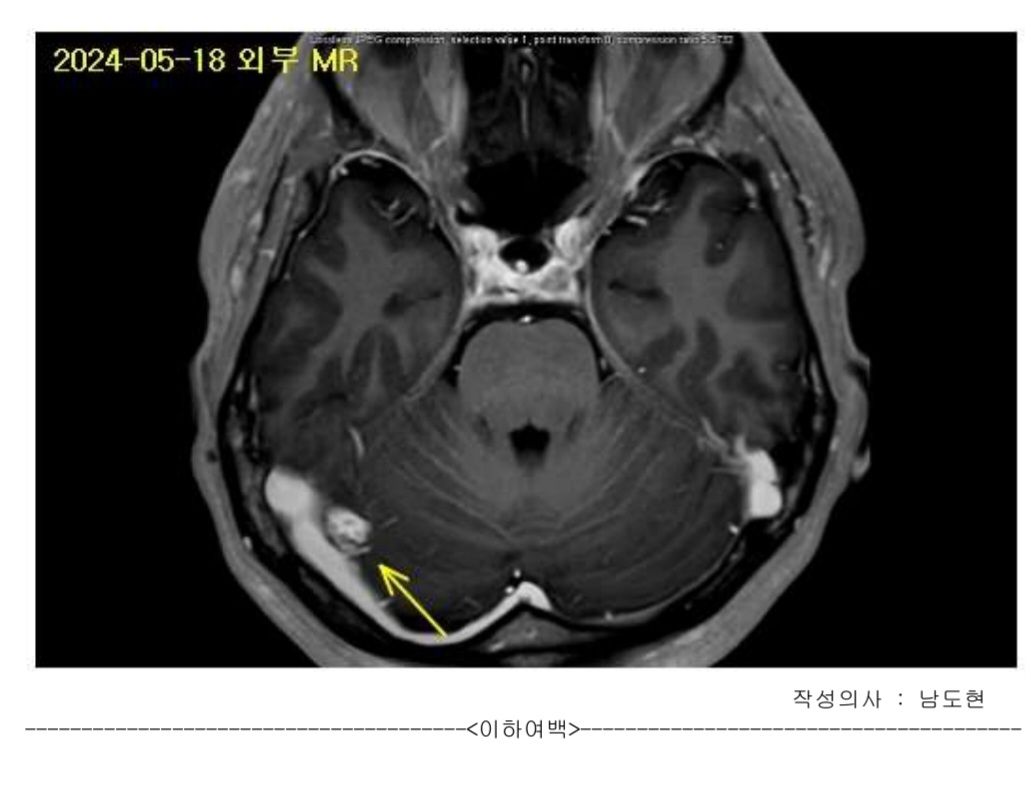

• MRI 판독 결과에 따르면, 오른쪽 천막부위에 약 1.6cm 크기의 이질적으로 조영되는 외축성 종괴 병변, 즉 수막종이 발견되었으나, 혈관이나 신경구조를 침범하지 않는 것으로 보입니다. 또한, 양쪽 대뇌 반구, 뇌간, 소뇌, 외축 공간에는 출혈이나 중양, 허혈성 병변이 없으며, 뇌 위축이나 수두증도 없는 상태입니다. 이러한 결과는 대체로 비교적 양호한 상태로 평가됩니다. 수막종은 대개 천천히 성장하는 양성 종양으로, 현재 대부분의 대학병원 교수님들이 6~12개월 간격으로 추적 관찰을 권장한 것도 이와 같은 이유에서입니다. 갑자기 크기가 커질 가능성은 낮지만, 드물게 급격히 성장하거나 증상이 나타날 수 있으므로 정기적인 추적 관찰이 중요합니다. 지금으로서는 급한 치료나 조치는 필요하지 않지만, 정기적으로 MRI 검사를 통해 종양의 크기 변화를 모니터링하고, 두통, 시야 변화, 운동 이상 등 새로운 증상이 나타나면 신경외과를 방문하여 상담받는 것이 좋습니다.